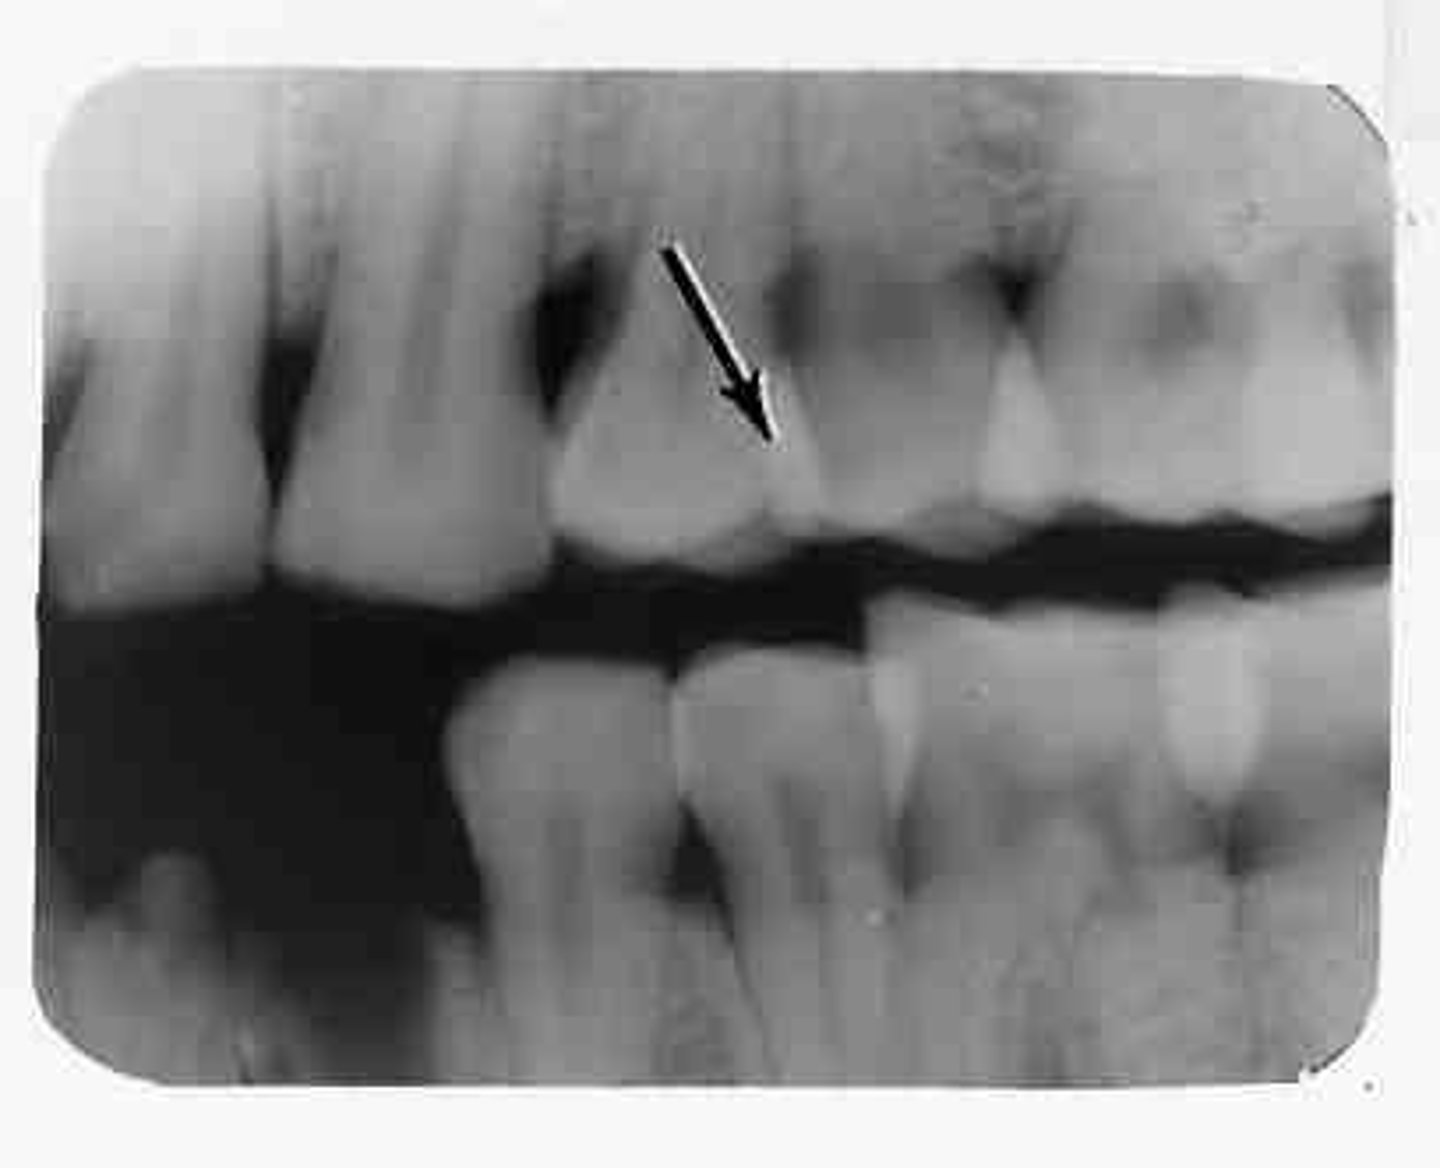

What causes overlap of interproximal spaces on an image?

Incorrect horizontal angulation.